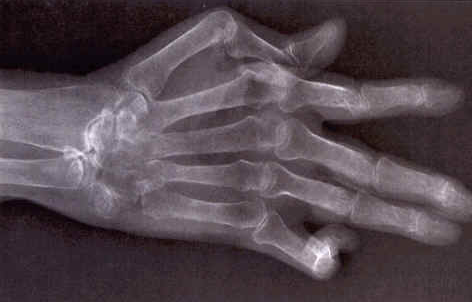

导读: 类风湿性关节炎表现为持续6周以上的对称分布的四肢小关节受累,一般可累及5个以上的关节部位,并有明显的晨僵症状。类风湿关节炎早期,关节因持续性肿胀而活动受限;晚期可出现关节畸形及强直固定。

导读: 隐匿型:占类风湿关节炎的60%-70%,典型起病常于数周或数月内逐渐起病,表现为掌指关节和腕关节的疼痛、肿胀和僵硬,可伴全身不适和乏力、低热、食欲不振、体重下降等。